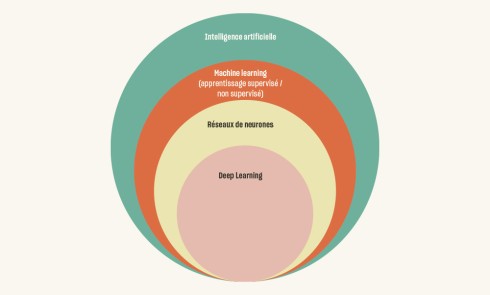

L’amélogenèse imparfaite est le nom donné à un groupe hétérogène de pathologies caractérisées par un défaut inné du développement de l’émail affectant toutes les dents des deux dentures. Ce sont des maladies génétiques dont l’origine est la mutation d’un gène impliqué dans l’amélogenèse. À ce jour, plus de 200 mutations différentes ont été identifiées, ce qui explique des phénotypes très variés [1]. Selon le stade de la maladie, l’émail est hypoplasique (défaut quantitatif), hypominéralisé, ou hypomature (défauts qualitatifs) : il est fin, fragile, tâché ou dyschromique. L’intensité des défauts peut être légère (forme frustre) ou très sévère, allant jusqu’à une absence totale d’émail. Son aspect est altéré par des dyschromies, fractures ou irrégularités de surface (fig. 1-4).